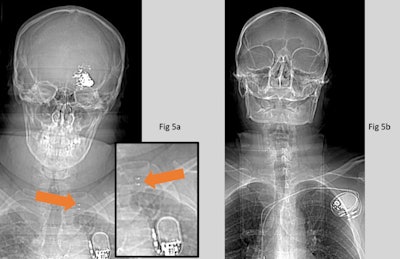

(Left) CT scout image of patient with vagal nerve stimulator (VNS). (Right) patient with pacemaker. Both active implants were recognized as such, but the VNS was incorrectly identified as a pacemaker. The VNS (5a) can be distinguished from a pacemaker (5b) by the metallic attachments to the vagus nerve (orange arrow). Any active implant poses a high risk in MRI and would need to be investigated thoroughly before proceeding. All images courtesy of Hannah Barnsley, Sam Chigozie Uzoukwu, Marco Borri, PhD, and the ISMRM.The ability to find and identify implants on radiological images is affected by both the quality of the image and the experience and skills of the reader, he explained. "In our study, the former was a limit only for a few implants -- those with both small size and fine mesh -- while the second affected a larger number of them. Both aspects should be optimized for effective screening."

Additionally, reader one missed an iliac stent and a breast clip. But from the list of implants included in this work, all high-risk implants that have led to documented injuries or death following MRI, such as aneurysm clips and active implants, were identified. All active implants were recognized as such. But in some cases, they were incorrectly identified (e.g., pacemaker instead of VNS, as shown in the first figure).